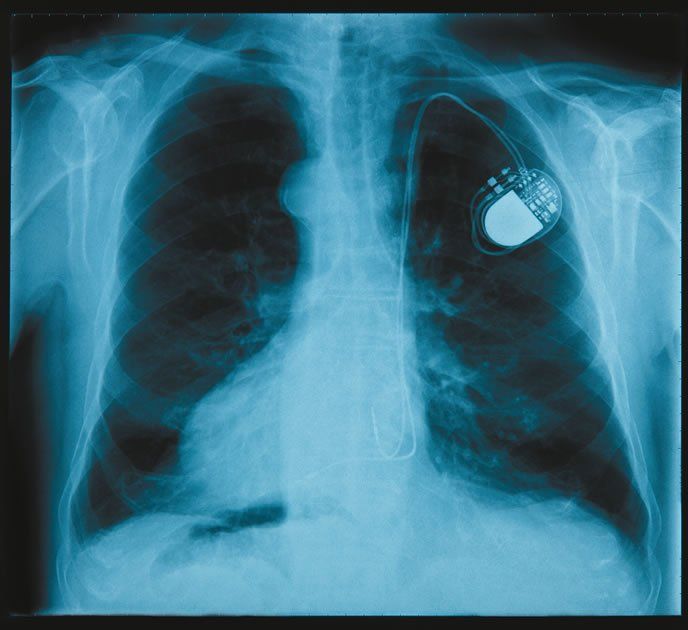

If a cardiac device, such as a pacemaker or an implantable cardioverter defibrillator (ICD), is in your future, youre probably already asking yourself or your doctor a lot of questions.